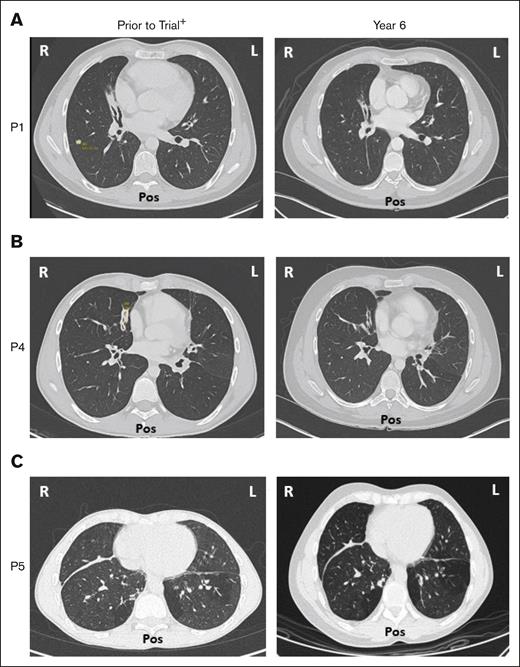

Five of 6 patients had a history of respiratory disorders. Half had bronchiectasis before receiving leniolisib; none progressed and all are stable at year 6 (Figure 7). Pulmonary function tests in 5 of 6 patients revealed no new or worsening conditions through year 6.

Bronchiectasis throughout treatment with leniolisib. Lung computed tomography scans from (A) P1, (B) P4, and (C) P5 who developed bronchiectasis before entry into the trial (left) and year 6 of treatment with leniolisib (right). L, left; Pos, posterior; R, right. +Images for P1 and P4 were taken ∼1 year before entry into the DFT, and the image for P5 was taken ∼4 years before exposure to leniolisib.